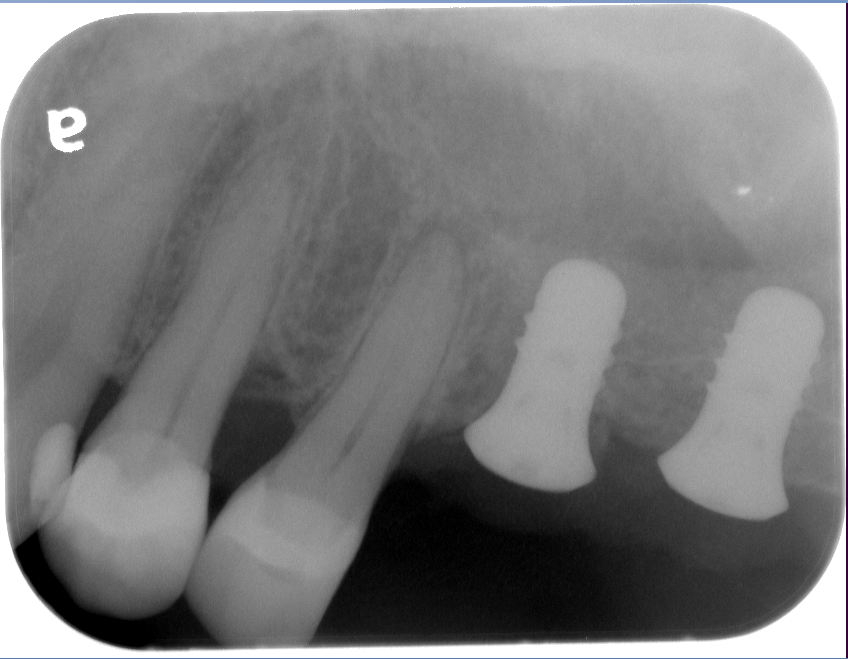

Sinus Lift Implant Vancouver Burnaby Periodontist Implant Dentist IMPreESS Perio

Dental Implant Centre in Vancouver Burnaby Sinus Lift Dental implant Surgery Dr. Noroozi Implant Specialist IMPrESS Perio Implant Center.001

Sinus Lift, Bone Graft, Implants Dr. Noroozi IMPrESS Perio Implant Center